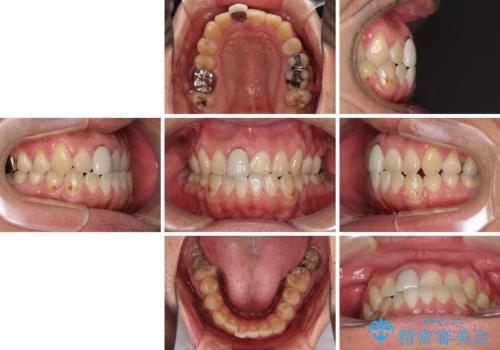

- 前歯のデコボコと上下のクロスバイトを気にして来院された患者様です。

インビザラインを用い、IPR(歯と歯の間を削る)と歯列全体を拡大させることで、歯並びを整えていくこととしました。

上の前歯が下の前歯を乗り越える際、奥歯がほとんど咬めない時期があり、乗り越えた後も、インビザライン特有の奥歯の咬みにくさが続きました。

咬み合わせ改善のために治療期間を要しましたが、最終的に奥歯はしっかりと咬めるようになりました